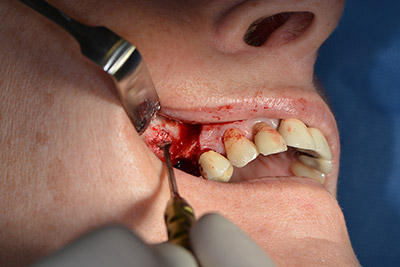

Le vie indicate di seguito sono realizzate con una perforazione a velocità ridotta, pari a 300 rpm. In questa fase Implantmed dimostra la sua grande affidabilità. È possibile predefinire il protocollo chirurgico: per selezionare le varie posizioni, basta premere la lettera “P” con il controllo a pedale (da fig. 10 a 11).

Il passaggio successivo consiste nel posizionamento dell'impianto, che nel nostro studio prevede una potenza pari a 32 Ncm (fig. 12).